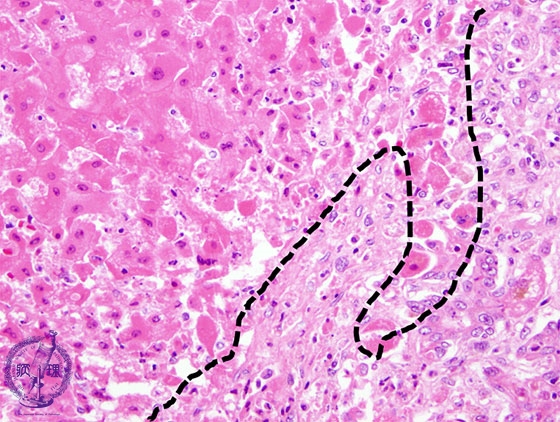

- ★(3)Fulminant hepatitis

Microscopic image (HE stain, high power): There is an interface between necrotic (left of the dotted line) and non-necrotic areas; the necrotic hepatocytes are swollen and more eosinophilic.